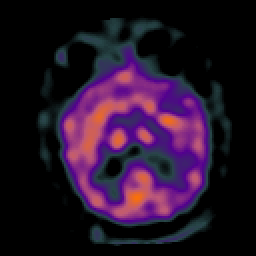

Subacute Stroke, overlay -- Slice #13

[Home][Help][Clinical] Slice 13